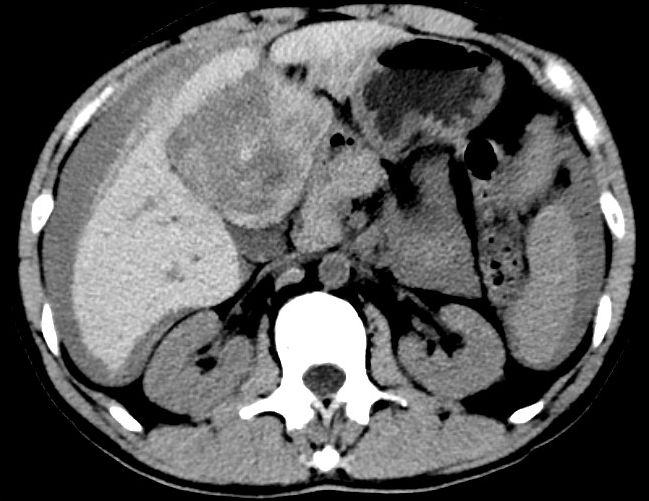

放下電話的白葦急赴消內(nèi)三搶救室會(huì)診,經(jīng)仔細(xì)查體、對(duì)患者腹部CT進(jìn)行詳細(xì)閱片、綜合評(píng)估患者后,考慮患者是肝占位破裂出血?;颊卟∏槭志o急、一刻也不容耽誤,需立刻急診行肝動(dòng)脈造影 栓塞術(shù)進(jìn)行止血治療,在與患者家屬溝通后,立即通知消化介入室準(zhǔn)備急診手術(shù)。

入手術(shù)室時(shí),患者神志迷糊,口唇干燥、重度貧血貌,心電監(jiān)護(hù)提示:心率140-160次/分,血壓70/43mmHg,這是失血性休克的表現(xiàn)!白葦快速建立靜脈通道緊急給予輸血,升壓,止血等液,立即給予肝動(dòng)脈造影,術(shù)中發(fā)現(xiàn)肝左葉疑似腫瘤病灶、病灶周圍血管分支有造影劑外溢,考慮血管破裂出血,迅速給予栓塞微球進(jìn)行肝動(dòng)脈栓塞。整個(gè)手術(shù)過程不足20分鐘,術(shù)后即刻患者心率降至100-110次/分、血壓升至90/60mmHg。

術(shù)后給予積極抗炎,止血,保肝、利尿等對(duì)癥治療,復(fù)查血常規(guī)提示活動(dòng)性出血停止后,在超聲引導(dǎo)下行腹腔穿刺引流術(shù),術(shù)后3天共引流出血性腹水約4000ml?;颊呓?jīng)復(fù)查各項(xiàng)指標(biāo)均趨于正常,復(fù)查CT提示腹腔積血已基本吸收,患者康復(fù)出院。